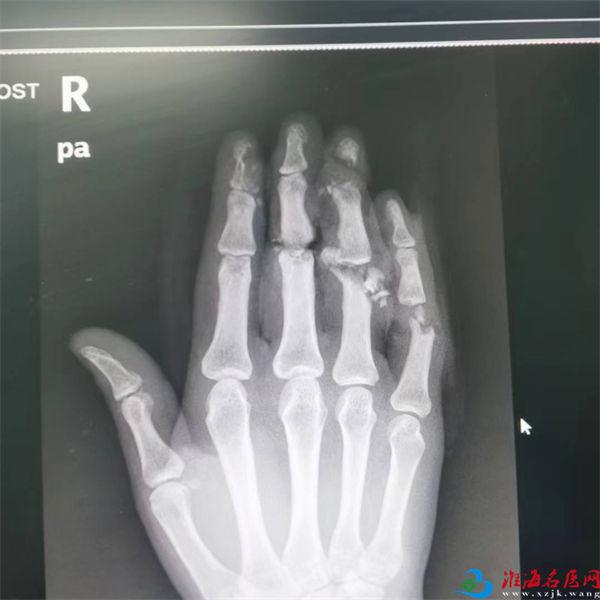

L女士老家安徽,在徐州某家具公司务工。受伤后,被工友迅速送至徐州一院急诊外科,因需要紧急手术救治,值班医生进行伤口初步处理和影像学等检查后,一边紧急联系手足显微外科专家团队,一边迅速开通绿色通道,将患者直接送至徐州一院烧伤整形创面修复及手足显微外科病区。触目惊心的伤情让手足显微外科专家张希龙印象异常深刻。

右手食指中远节尺侧见一不规则挫裂伤口,创缘不齐,部分皮肤软组织缺损,甲床部分缺损,创面内软组织挫伤严重,远节指骨尺侧纵行骨缺损;

右手中指近侧指间关节见一不完全离断伤,仅背侧皮肤软组织及伸肌腱连接,掌侧切割伤口挫裂严重,软组织挫伤严重伴缺损,近侧指间关节粉碎性骨折伴缺损,屈肌腱及两侧指动脉神经断裂,远端血运差;

右环指于近、远侧指间关节处各见一不全离断伤,仅屈肌腱及部分皮下软组织连续,伤口挫伤严重,部分软组织缺损,近、远侧指间关节粉碎性骨折伴缺损,伸肌腱及两侧指动脉神经断裂伴缺损,指端苍白冷瘪;

右小指近侧指间关节见一不全离断伤,仅桡侧少许皮下软组织连续,伤口内软组织挫伤严重,近侧指间关节粉碎性骨折伴缺损,屈、伸肌腱及两侧指动脉神经断裂,指端苍白无血运,远节指两侧另见大小不等不规则挫裂伤口;

各创面有不同程度活动性出血,同时伴有部分绿色粉尘异物存留。

患者的伤情需要立即进行断指再植术。而手术效果不但和医生的手术技术有关,还和断指伤情、手术时机关系密切。